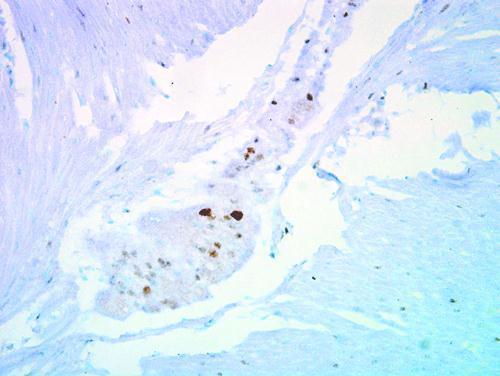

Supportive validation

- Submitted by

- Invitrogen Antibodies (provider)

- Main image

- Experimental details

- Immunohistochemical staining of human ulcerative colitis tissue using anti-p27 Kip1 Polyclonal Antibody (Product # PA5-27188).